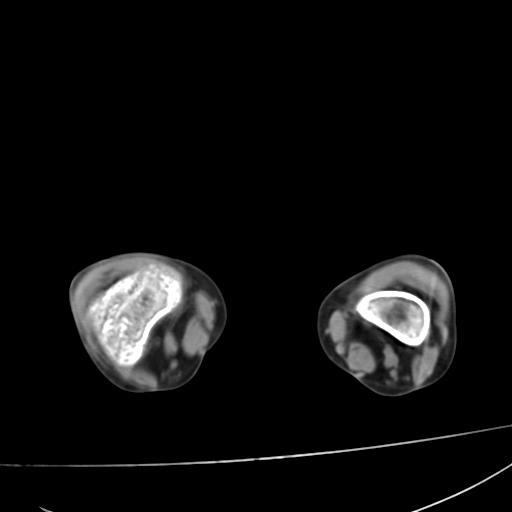

标题: PED0940:M12Y,左股骨下端酸痛畸形 [打印本页]

标题: PED0940:M12Y,左股骨下端酸痛畸形

12岁男孩,左膝关节肿痛8年,近月明显

内生骨软骨瘤?

血友性关节病?